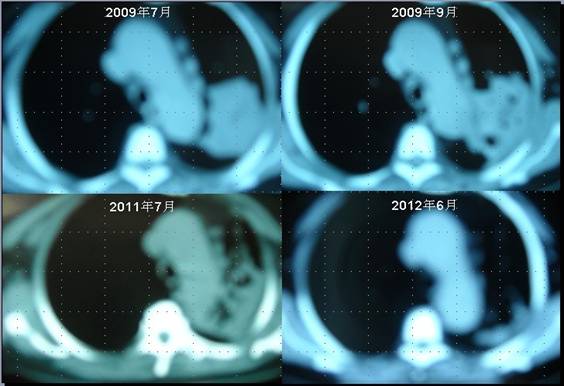

患者李某某,女,64歲,于2009年6月因咳嗽、喘憋、痰中帶血,經(jīng)CT及病理等相關(guān)檢查確診為右肺上葉粘液腺癌,縱膈淋巴結(jié)轉(zhuǎn)移, 左胸膜轉(zhuǎn)移,胸腔積液,因病情及體質(zhì)的原因無(wú)法接受手術(shù)及放化療等殺傷性治療,采用“中醫(yī)調(diào)胃、強(qiáng)腎、止血、化巖法”先后共治療8個(gè)月,現(xiàn)患者已有質(zhì)量的存活近3年。目前隨訪患者飲食、睡眠、體力均好,可獨(dú)立完成日常家務(wù),如今患者已經(jīng)67歲。

肺癌病人李XX采用“董氏治癌法”治療前后CT變化